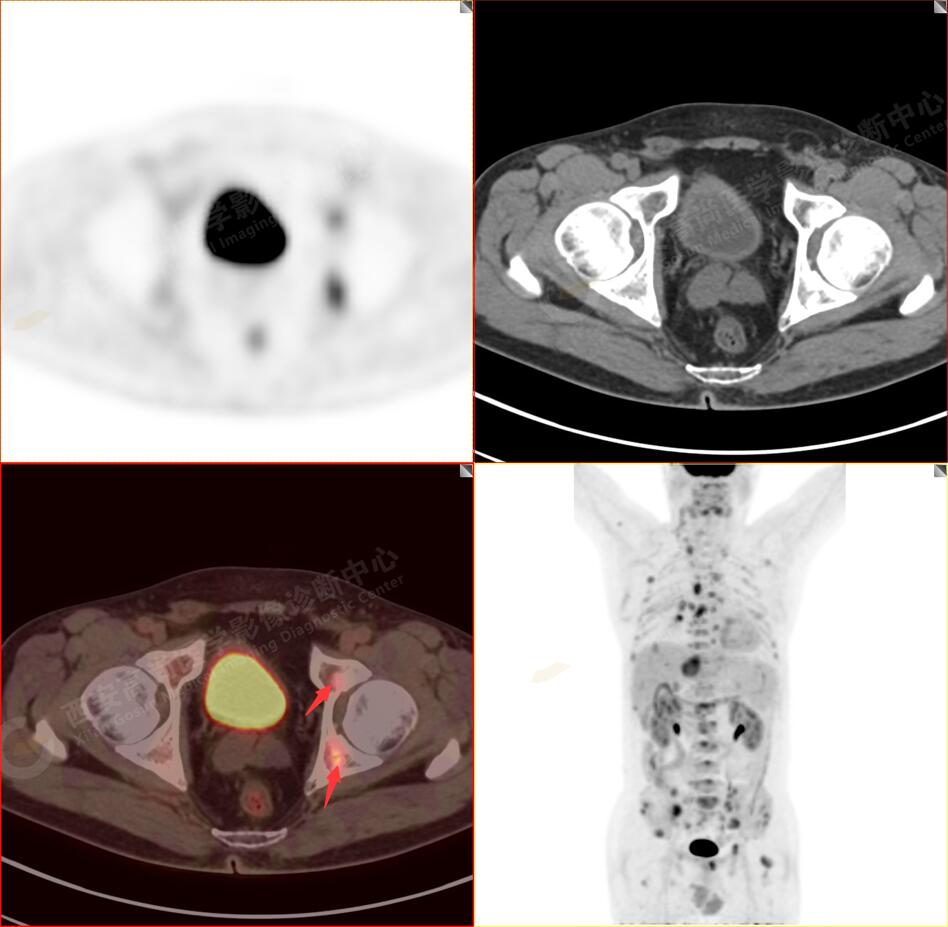

2.以下為全身多發(fā)轉移灶

4.肝S4、8段團塊狀及結節(jié)狀低密度病變,以S4段病變?yōu)橹什煌潭菷DG代謝異常增高,考慮為肝多發(fā)轉移。

5.右側肱骨上段、左側肩胛骨、右側鎖骨胸骨端、胸骨、雙側多發(fā)肋骨、脊柱多發(fā)椎體及附件、雙側髂骨、雙側髖臼、雙側恥骨、雙側肱骨上段多發(fā)成骨性病變,呈不同程度FDG代謝異常增高,考慮為多發(fā)骨轉移瘤。